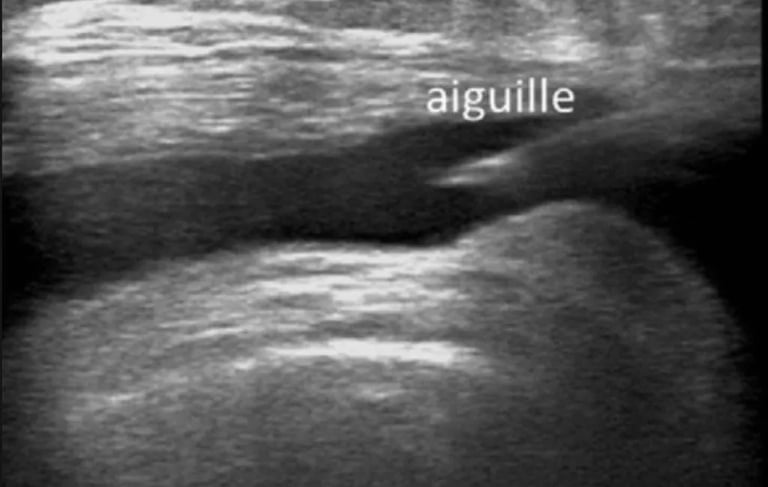

✔ Contrôle échographique en temps réel

Repérage précis à l’échographie

Ponction du liquide (si nécessaire)

Infiltration ciblée du traitement